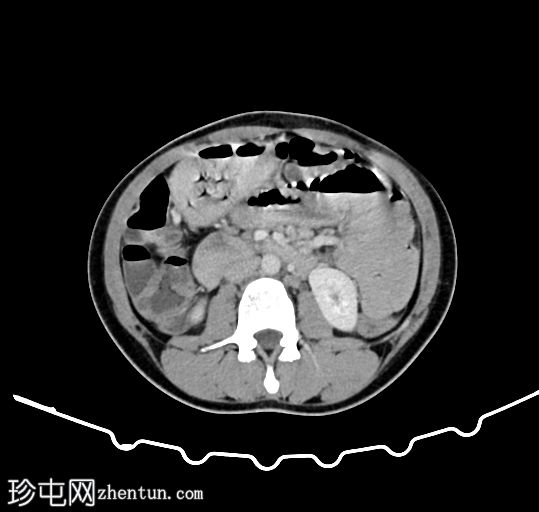

轴向C+门静脉期

小肠中央可见曲线/管状充盈缺损,因运动而略微模糊。小肠轻度增厚。其他检查正常。

地方性人群中小负担蛔虫病的典型表现,小肠轻度(相对轻微,甚至可能不明显)增厚,小肠中央可见特征性的管状曲线充盈缺损。